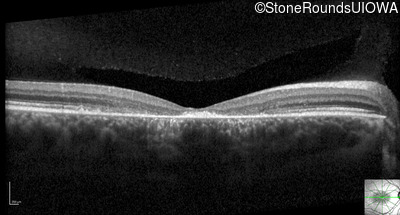

Optical Coherence Tomography - Right - 10/125 -1

Exemplar / OCT Stack

OCT Stack